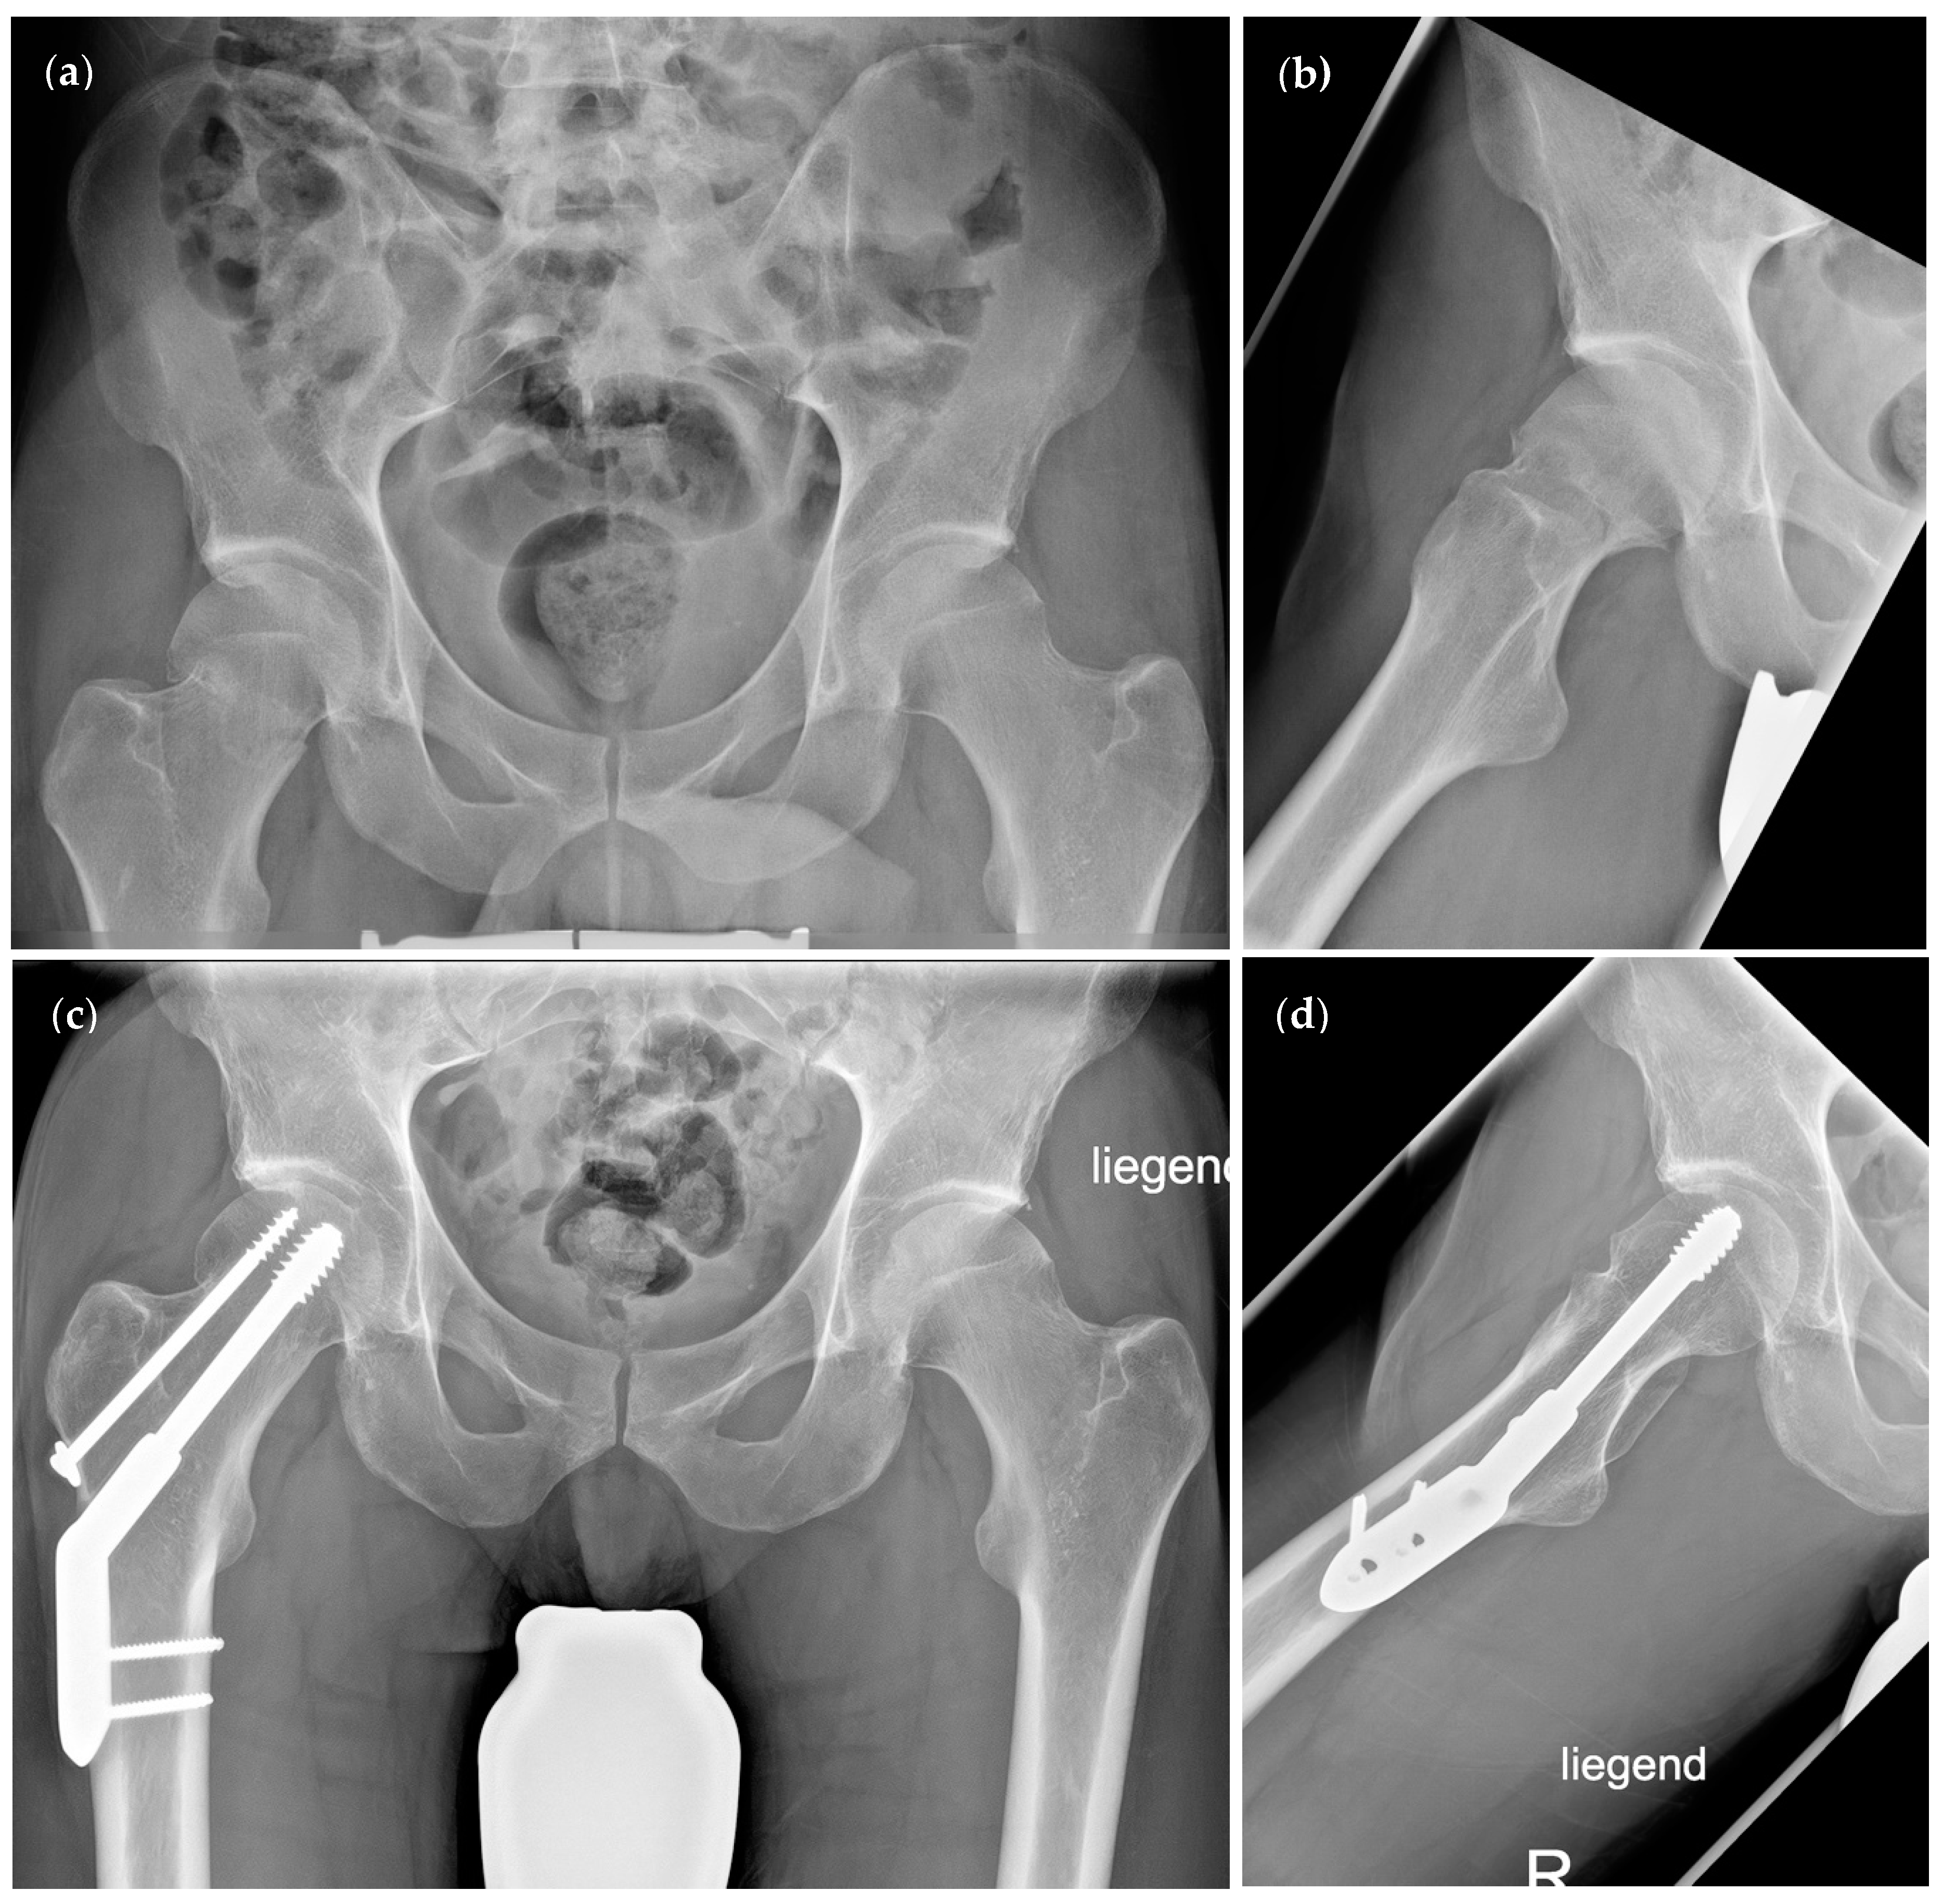

| Preoperative Pauwels angle (°) | 50.93 ± 14.07 | 47.66 ± 14.44 | p = 0.41 | |

| (95% CI 44.15–57.71) | (95% CI 38.49–56.83) | |||

| Postoperative Pauwels angle (°) | 46.74 ± 7.71 | 43.34 ± 7.93 | p = 0.22 | |

| (95% CI 43.03–50.46) | (95% CI 38.3–48.38) | |||

| Preoperative CCD angle (°) | 129.5 ± 16.21 | 130.8 ± 13.25 | p = 0.8 | |

| (95% CI 121.7–137.3) | (95% CI 122.4–139.2) | |||

| Postoperative CCD angle (°) | 135.9 ± 7.27 | 136 ± 5.24 | p = 0.85 | |

| (95% CI 132.4–139.4) | (95% CI 132.7–139.4) | |||

| Pauwels classification | Type I (% of group) | 1 (5.26%) | 1 (8.33%) | p = 0.72 * |

| Type II (% of group) | 10 (52.63%) | 7 (58.33%) | ||

| Type III (% of group) | 8 (42.11%) | 4 (33.33%) | ||

| Garden classification | Type I (% of group) | 2 (10.53%) | 1 (8.33%) | p = 0.45 ** |

| Type II (% of group) | 9 (47.37%) | 8 (66.67%) | ||

| Type III (% of group) | 4 (21.05%) | 2 (16.67%) | ||

| Type IV (% of group) | 4 (21.05%) | 1 (8.33%) | ||